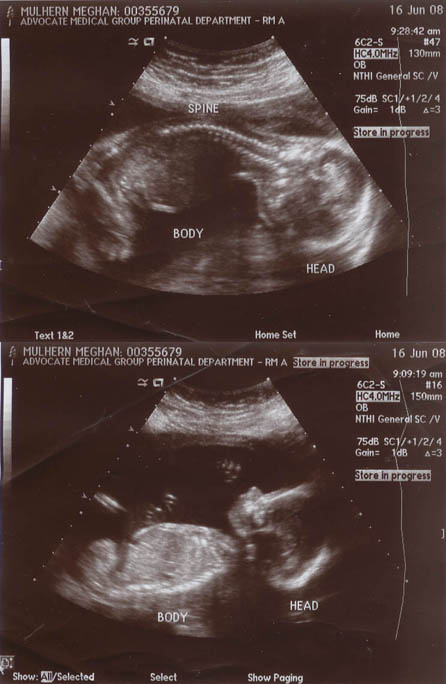

21 Week Ultrasound